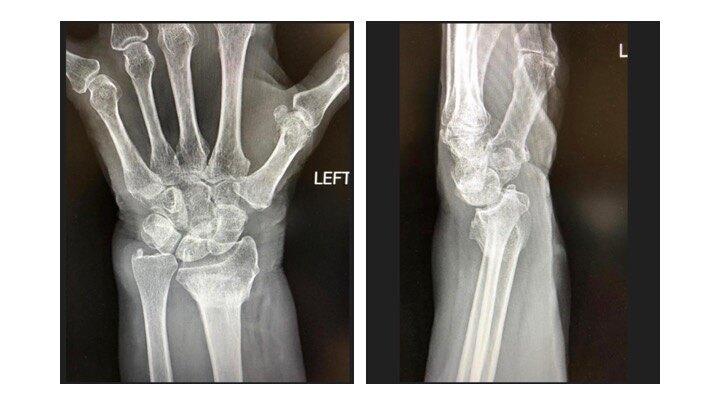

左手桡骨远端骨折图,正常左手桡骨远端图片

复位后拍片:左桡骨远端骨折,对位对线良好.

林莲菊,摔伤左手桡骨远端骨折病例

左桡骨远端骨折图片

左手桡骨远端骨折图片

左侧桡骨远端骨折图片

左尺桡骨远端骨折图片